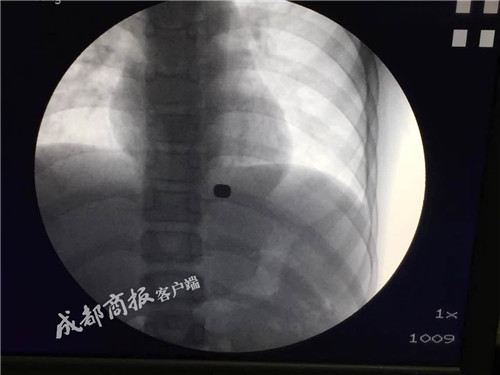

伴隨著胸腹部傳來的劇痛,小強將自己誤吞磁鐵的事情告訴了父母。到醫院一檢查,才發現跌落在小強食管下段賁門處的磁鐵,與掉落在胃底的磁鐵隔著胃底肌層緊緊相吸,同時還鑿出一個0.1厘米的穿孔。因為長時間停留,賁門和胃底部的組織已經將兩塊磁鐵“包裹”起來,磁鐵深深嵌入肉里,根本看不到磁鐵的邊緣。此時醫生的建議是:開胸手術,取出磁鐵。而父母擔心強強年齡過小,無法承受如此大的手術,于是輾轉云貴兩省多家醫院,無奈都得到了相同的答案:只能開胸。

11月7日上午11點,麻醉后的強強被推進手術室,胡兵先用內鏡從他的食道伸進去,輕輕撥開包裹著兩塊磁鐵的組織,然后再把嚴格消毒后的“磁王”套上一根細線,用內鏡緩緩送到強強體內的磁鐵旁。不出所料,一個小時后兩塊磁鐵被成功取出。